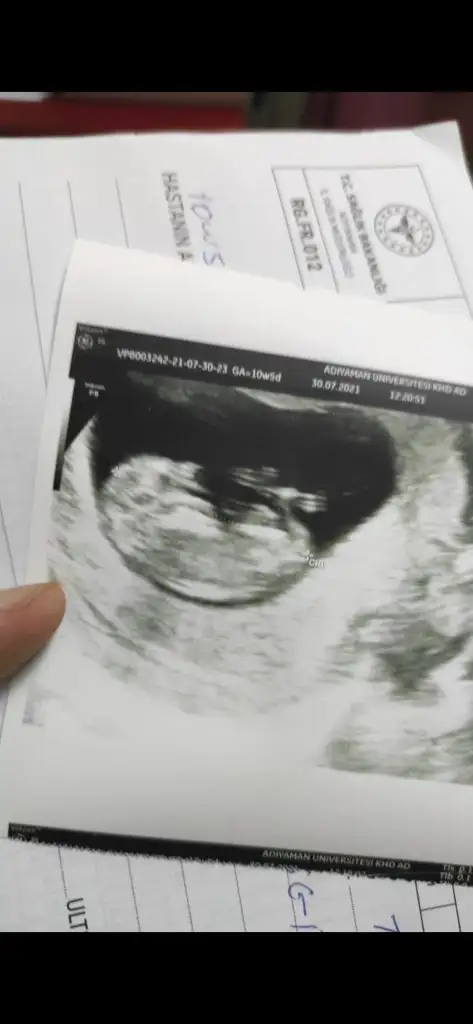

11+3 ultrasonuna göre tahmininiz nedir?10 haftaya göre kız ama en iyi 11 12 13 haftalar olmalı tekrar USG paylasin![]()

11+3 e göre tahmininiz nedir?10 haftaya göre kız ama en iyi 11 12 13 haftalar olmalı tekrar USG paylasin![]()